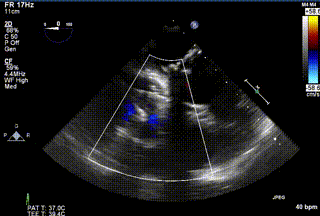

三例患者入院后,葛均波院士團隊周達新教授、潘文志教授、張源博士、陳莎莎博士及心超室的潘翠珍教授、李偉教授對患者的情況進行詳細評估和討論,最終決定為三例患者選擇LuX-Valve Plus40mm、50mm和50mm型號的瓣膜進行手術治療。手術后即刻拔除氣管插管,術后患者三尖瓣反流癥狀得到顯著改善,復查心超結果顯示人工三尖瓣瓣膜支架固定穩定,瓣葉關閉形態未見異常,未見明顯反流。